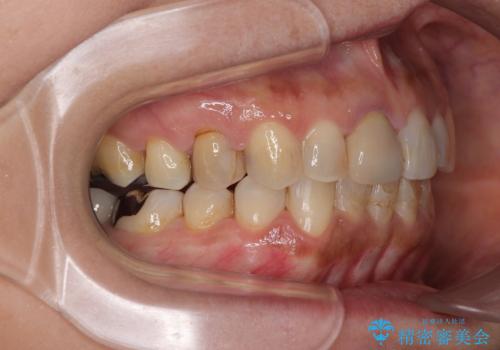

痛みがなくなり歯列が整ったことで、残っている銀歯も気になり始めているようです。

マウスピース生活に疲れてしまったとのことで、暫くお休みをしてから銀歯の治療を再開していく予定です。